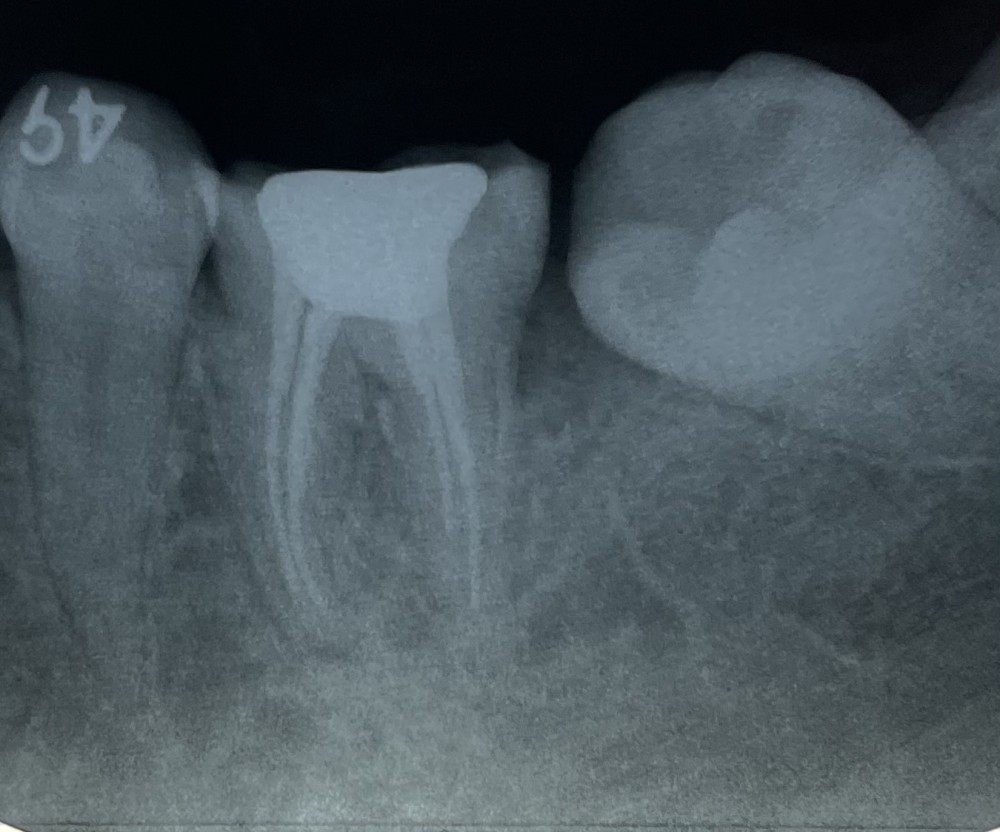

今回は、修復象牙質の添加(しゅうふくぞうげしつのてんか)による、遠心根の根管狭窄および、近心根管の湾曲の見られる歯の治療を紹介します。

上のエックス線写真で、真ん中に写っている歯には白く見える金属製の修復物が見られます。

修復物の下に虫歯ができてしまい、再治療する必要が生じました。

根管の狭窄と湾曲が認められます。